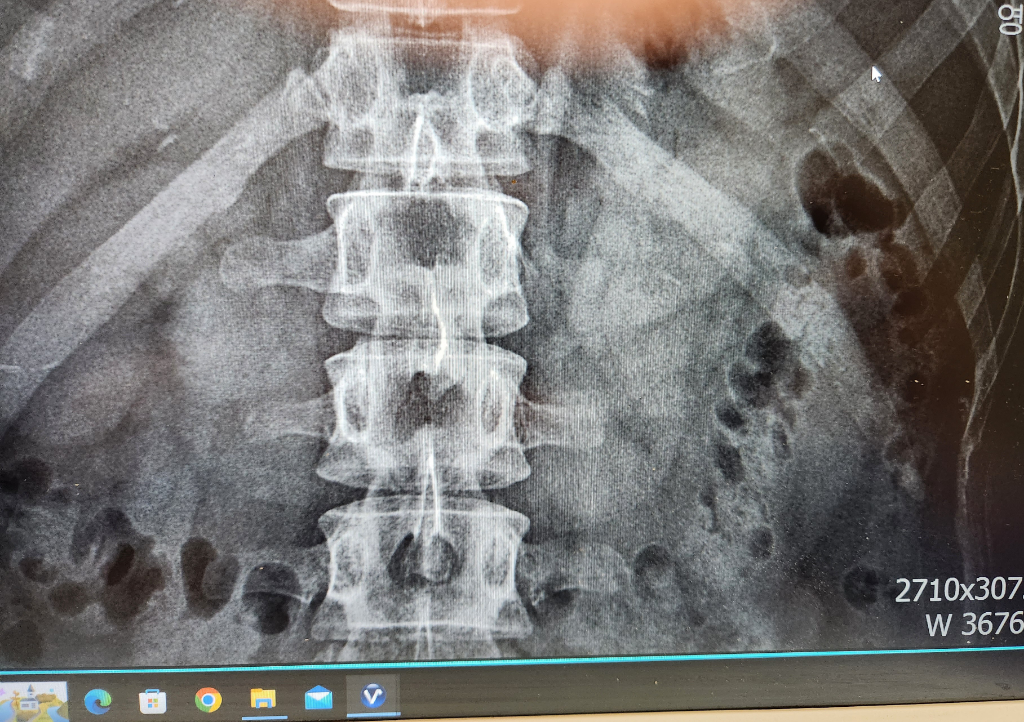

이거 12번 갈비뼈 골절 맞나요?

12번 갈비뼈 쪽에 통증이 있고 눌러봤을때 달그락 소리도 나서

Ct랑 엑스레이 찍어봤는데 이상이 없다고 하네요

제가 의사는 아니지만 제 생각에 이게 골절증상이 확실한거같아

영상자료를 cd로 받아와서 직접 봤는데 제눈에도 보이는데 이게 골절이 아닌가요..?

사진의 소견을 통해서 보았을 때에 좌측의 12번 갈비뼈의 골절이 굉장히 의심스런 선이 보입니다. 해당 부위의 증상이나 엑스레이 소견으로 볼 때에 충분히 골절이라고 볼 수 있습니다. 한방은 전문성이 떨어지기 때문에 흉부외과적으로 진료를 보시는 쪽을 더 권고드립니다. 다만 갈비뼈 골절에 대해서는 스스로 붙을 때까지 추가적인 손상을 예방하고 환부를 쉬어주는 것이 최선의 치료법이기 때문에 병원에 가신다고 하여 특별한 것이 있지는 않을 것이며 진통제를 복용하며 경과를 지켜보는 것이 현재로서는 적절한 치료법입니다.

X-ray 로 봤을 때에도 왼쪽 12번째 갈비뼈 골절의 가능성이 있는데 현재 보이는

부분은 앞쪽 갈비뼈가 아닌 등쪽 갈비뼈에 해당됩니다. 등에 통증이 있고 그 부분에서

소리가 들리는 경우 골절이 맞는 것으로 보이는데 CT 를 찍었다면 골절 여부를 확인하는

가장 정확한 검사는 Chest CT 이기 때문에 이를 확인하는 것이 좋습니다.